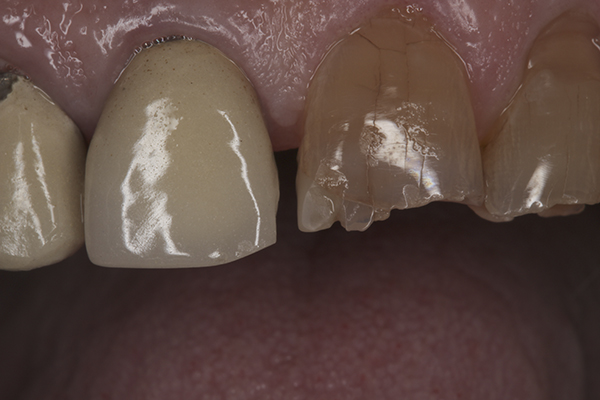

(26.) Provisionals, right anterior, close-up view.

Figure 26

(27.) Provisionals, anterior, close-up view.

Figure 27

(28.) Provisionals, left anterior, close-up view.

Figure 28